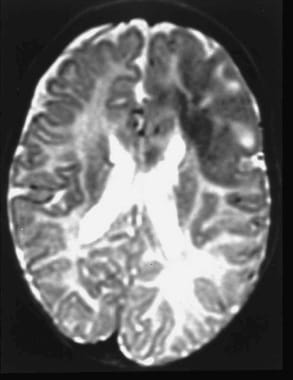

Multiple tubers in a child with tuberous sclerosis, normal intelligence, and well-controlled seizures. High tuber count does not invariably mean poor neurological outcome.

All tubers are not equal. This child has a smaller number of tubers than the patient shown in the previous image, but the tubers are larger in size. She too has normal intelligence and is seizure free on medication.